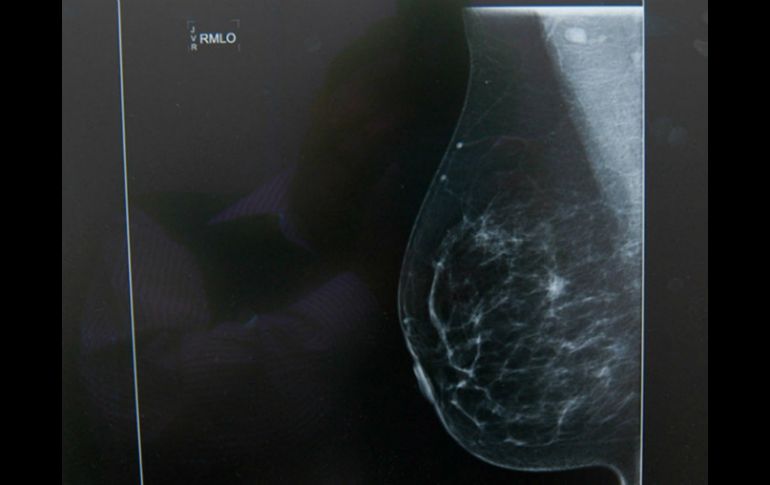

Tecnología | La técnica con el uso de una imagen de termografía registra los tejidos anormales Detectan cáncer de mama con temperatura corporal La técnica con el uso de una imagen de termografía registra los tejidos anormales Por: NTX 24 de enero de 2016 - 15:24 hs El método de exploración, además de no se invasivo permite la detección de esta enfermedad. NTX / ARCHIVO CIUDAD DE MÉXICO (24/ENE/2016).- Un investigador de la Universidad Autónoma de San Luis Potosí (UASLP) desarrolló una técnica para detectar a tiempo el cáncer de mama con el uso de una imagen de termografía, tecnología que registra de manera gráfica la temperatura del cuerpo. En entrevista para la Agencia Informativa del Consejo Nacional de Ciencia y Tecnología (Conacyt), el especialista Francisco Javier González Contreras explicó que este método tiene un nivel de efectividad superior a 90 por ciento. "Los tumores cancerosos, específicamente el de cáncer de seno, tienen una generación de calor metabólica más alta porque las células se reproducen más rápido que en el tejido normal", dijo el especialista. "Esas variaciones de temperatura se pueden ver a través de la termografía infrarroja", agregó. Este método de exploración clínica, además de no ser invasivo, permite la detección de formaciones anormales menores a seis milímetros de diámetro y a una profundidad de dos centímetros en el seno. "Si tomamos en cuenta que el principal método que se promociona es la autoexploración, una mujer no nota una 'bolita' hasta que mide más o menos un centímetro, y ya para cuando llega una persona con una formación de este tamaño, el tumor pudo haber estado creciendo de tres a cinco años", subrayó el médico. Considerado por la Administración de Alimentos y Medicamentos (FDA, por sus siglas en inglés) como un método de diagnóstico adjunto, el investigador dijo que se recomienda complementar esta técnica con el ultrasonido para obtener un diagnóstico más certero. Lo anterior, dijo, porque esta técnica aún no está avalada para determinar la presencia de esta enfermedad. El ganador del Premio Nacional de Investigación 2012 sostuvo que a pesar de que la termografía existe desde la década de los 80, es poco utilizada en la detección de cáncer. "No obstante, el desarrollo tecnológico y los avances en las cámaras termográficas han resultado en mejores imágenes y, en consecuencia, en diagnósticos más acertados", afirmó. El académico describió que el método más utilizado para la detección de cáncer de mama es la mamografía, radiación que arroja una imagen anatómica del seno mediante la cual se pueden observar formaciones atípicas en el tejido. "La mamografía es un estudio anatómico, mientras que la termografía infrarroja es un análisis funcional del seno. La unión de las partes anatómica y funcional es la que daría un mejor diagnóstico", apuntó. Por ello, la forma más efectiva para detectar la enfermedad en una etapa temprana es la suma de la termografía y el ultrasonido, aseguró el especialista. Otra de las ventajas de la termografía clínica es que se puede utilizar en mujeres de cualquier edad, ya que al contrario de la técnica por mamografía, la interpretación de las imágenes no se dificulta por los senos densos, presentes en mujeres más jóvenes o bajo terapias hormonales. Parte del proyecto en el que trabaja González Contreras consiste en llevar este método de detección de cáncer a comunidades donde no hay centros de salud para realizar un primer diagnóstico. Además, buscan canalizar a las pacientes para estudios más profundos y así disminuir la tasa de mortalidad por esta enfermedad. Temas Ciencia médica Cáncer de mama Enfermedades Calor de hogar Salud general Lee También ¿Cuánto tarda una persona con depresión en llegar al tratamiento? Razones por las que beber agua mineral en exceso afecta tus huesos y dientes ¡Toma nota! 5 razones para lavar los trastes en casa con sal 5 motivos por los que DEBES tener un vaso de agua junto a tu cama al dormir Recibe las últimas noticias en tu e-mail Todo lo que necesitas saber para comenzar tu día Registrarse implica aceptar los Términos y Condiciones